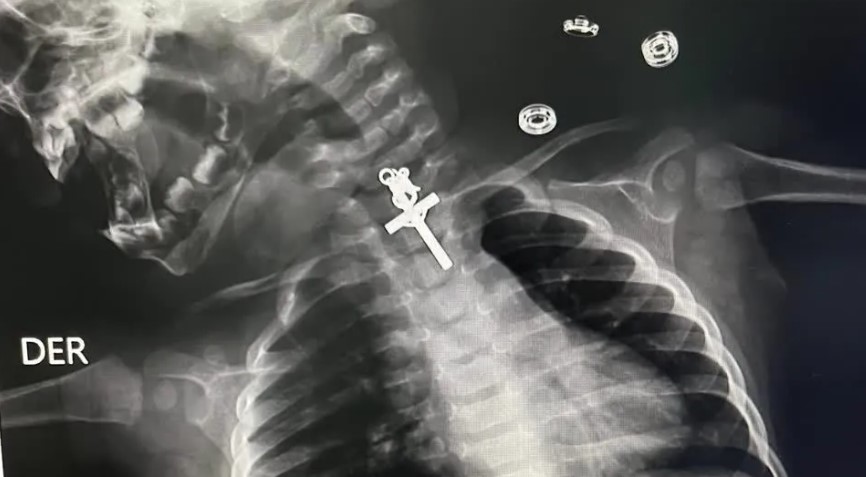

Imagens de raio-X mostraram um crucifixo alojado no esôfago de um bebê de 10 meses. A criança foi atendida no Hospital Victor Lazarte Echegaray, em La Libertad, no Peru, onde foi submetida a uma endoscopia para retirada do corpo estranho.

O artefato foi removido com sucesso pela equipe médica no sábado (11).

“O procedimento foi muito complicado porque era um crucifixo e estava alojado no terço superior do esôfago. Mesmo quando tentamos retirá-lo inicialmente, não conseguimos, estava preso, então tentamos várias vezes até que consegui retirar o corpo estranho”, disse o médico responsável, Luis Esteves Cabanillas.